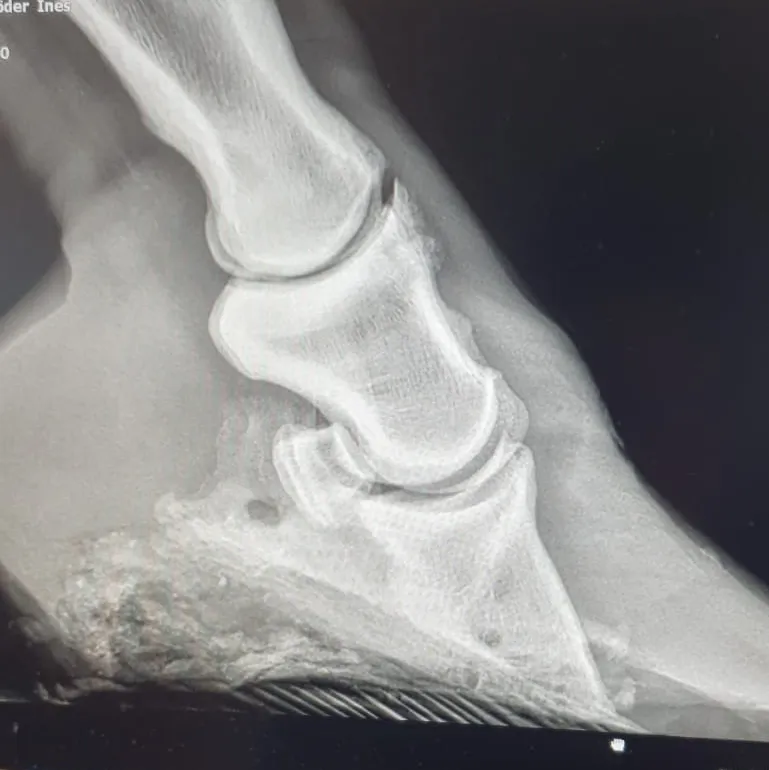

Warum Röntgen Pflicht ist

Nur eine Röntgendiagnostik zeigt eindeutig:

Ob eine Hufbeinrotation vorliegt

Ob eine Hufbeinabsenkung geschehen ist

Wie stark die Schädigung ist

Alles andere ist Spekulation – und kostet wertvolle Zeit, in der sich der Zustand rapide verschlechtern kann.